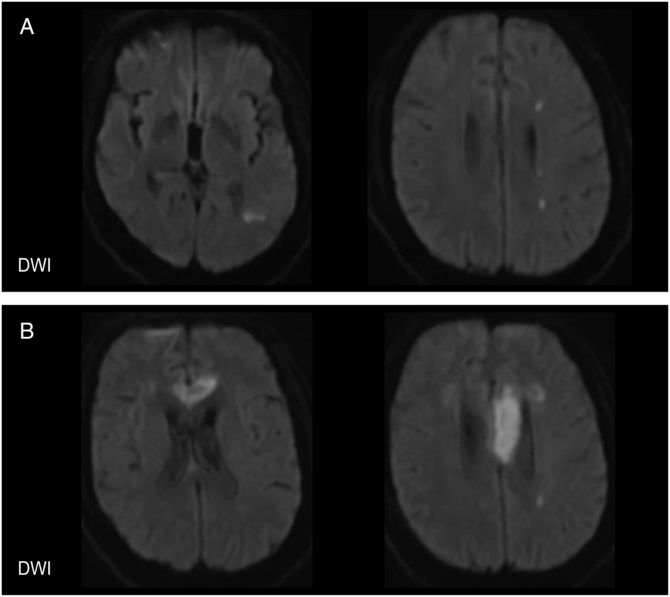

Computed tomography (CT) demonstrated a remote infarct in the anterior limb of the right internal capsule and corona radiata, and chronic microangiopathic white matter changes in both cerebral hemispheres, but no acute abnormalities. CT angiography (CTA) demonstrated complete occlusion of the left internal carotid artery (ICA), extending 1 cm from its origin to the cavernous segment, and occlusion of the left vertebral artery, extending from its origin to the level of the C5 vertebral body (Figure 1). There was also 50% stenosis of the right ICA at the origin. The circle of Willis was patent. Brain magnetic resonance imaging (MRI) the following day demonstrated acute ischemic infarcts involving the left parietal cortex and corona radiata in watershed territory (Figure 2A). Given the patient's occluded left ICA, the infarcts were thought to be secondary to large-artery atherosclerosis and thromboembolism. He was discharged with dual antiplatelet therapy using aspirin and clopidogrel and maintained on therapies for diabetes mellitus, hypertension, and dyslipidemia.

Figure 2: Brain MRI with diffusion-weighted imaging (DWI). (A) 1 day after the patient's initial presentation, MRI demonstrated acute infarction of the left parietal cortex (left) and corona radiata in a watershed distribution (right). (B) During the patient's second presentation, MRI demonstrated acute infarction of the anterior corpus callosum involving the left genu (left) and the body (right).

Two months later, the patient re-presented to hospital with acute-onset altered level of consciousness, mutism, a blood pressure of 140/80, and a random blood glucose of 3.4 mmol/L. His level of consciousness improved with the administration of dextrose, but his speech and language did not return to baseline. Language examination demonstrated occasional word finding difficulties, and slowed speech, hesitations, and articulatory errors consistent with an apraxia of speech. The remainder of the neurological examination was not significantly changed from his previous admission. CT and MRI demonstrated an acute ischemic infarct involving the left lateral aspect of the genu and body of the corpus callosum (Figure 2B). CTA did not show any interval change. Further workup with transthoracic echocardiogram and 48-hour Holter monitoring was unremarkable.

Regarding the mechanism of strokes in this patient, multiple CTAs demonstrated a persistently occluded left ICA with a proximal “stump.” Although the patient initially had multifocal infarcts suggestive of a thromboembolic process, cerebral hypoperfusion was a likely etiology for many of his infarcts and TIAs and was supported by impaired hemodynamics observed using CTP. The left brain relied entirely on collateral circulation given occlusion of the left ICA and vertebral artery, and the pattern of cerebral infarcts was consistent with cortical and deep border zone watershed infarcts. Furthermore, limb-shaking TIAs, or short-duration limb-shaking involving the upper or lower extremities, often associated with limb paresis and provoked by activities that reduce cerebral perfusion such as postural changes, are indicative of impaired hemodynamics in the brainReference Persoon, Kappelle and Klijn8 and are a risk factor for recurrent stroke in patients with ICA occlusion.Reference Persoon, Luitse and de Borst9 Concurrently, this patient had several infarcts that favored an embolic mechanism, including his ophthalmic artery occlusion and corpus callosum infarct. Although corpus callosum infarctions are rare and hypoperfusion cannot be excluded, the corpus callosum is supplied by the ACA, PCA, and abundant anastomoses, and infarction has been associated with large-artery atherosclerosis and thought to be embolic.Reference Li, Sun and Bai10 Taken together, this patient likely had multiple mechanisms for recurrent ischemia, which contributed to challenging management for secondary stroke prevention.